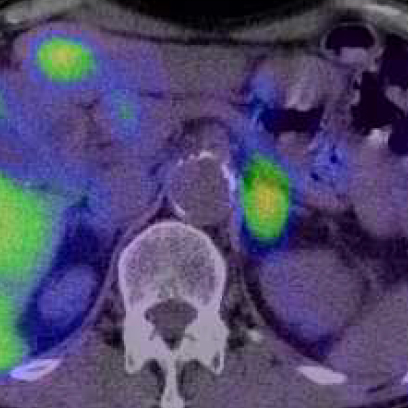

a. 123I-MIBG planar背面像

b. 単純CT

c. 123I-MIBG-SPECT/CT

図2 嚢胞変性した褐色細胞腫